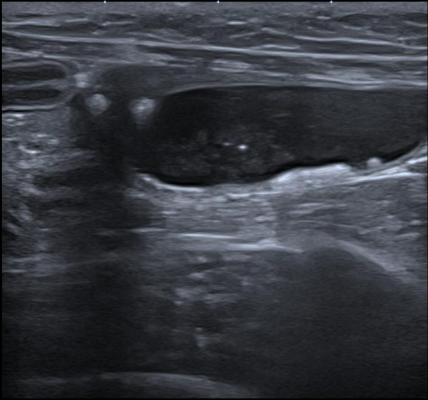

• Exposé théorique : sémiologie échographique, signes à rechercher et interprétation des principales lésions génitales.

• Mise en pratique à partir de vidéos de cas cliniques pathologiques de l’appareil génital :

• Identification des lésions

• Description avec la terminologie adaptée

• Synthèse des anomalies observées

• Élaboration du diagnostic différentiel